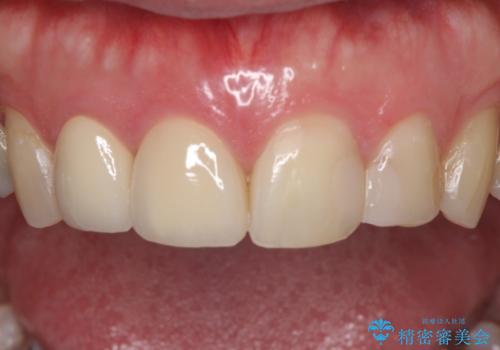

当初は1番目立つ1本だけをご希望でしたが、相談の結果、隣の歯(神経が抜いてあり金属が入っている歯)と2本同時に製作することになりました。

上の前歯など審美性の要求が高くなる部位については、数本同時に製作することで色をそろえることが可能です。

患者様は前歯の見た目の改善を主訴にご来院されました。上の前歯6本とも古いつめものがつぎはぎになっていましたが、まずは1番目立つところを治すことをご希望でした。相談の結果、今回は2本できれいになるように工夫しました。

患者様には大変満足して頂きました。